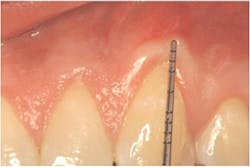

Secondly, gently retract the patient's lip or cheek to gain access, place the periodontal probe on the outside of the tissue, and measure from the gingival margin to the mucogingival junction, and record (see Figure 3).

Thirdly, measure the clinical probing depth (pocket depth to the sulcus) (see Figure 4). To calculate the attached gingiva, subtract the probing depth from the outside measurement of the gingiva for the total width of of attached gingiva. Record the width of the attached gingiva and identify any teeth that need tissue regeneration, such as root coverage surgery (see Miller classification I-III, Table 1).

Report to the dentist any teeth with recession that also have loss of attached gingiva width of less than 2 mm to indicate that root coverage surgery is recommended.